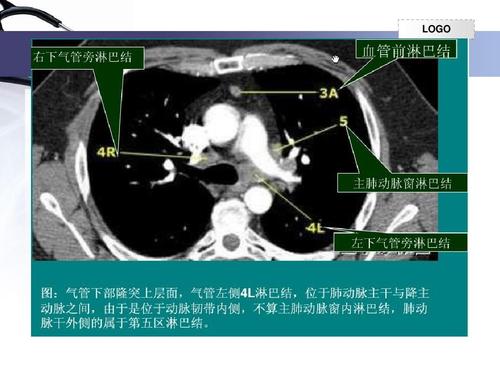

纵隔淋巴结新分区ctppt

纵隔淋巴结新分区ct

纵隔淋巴结ct片图解

纵隔淋巴结ct分区图谱

纵隔淋巴结分区图谱

纵隔淋巴结分区